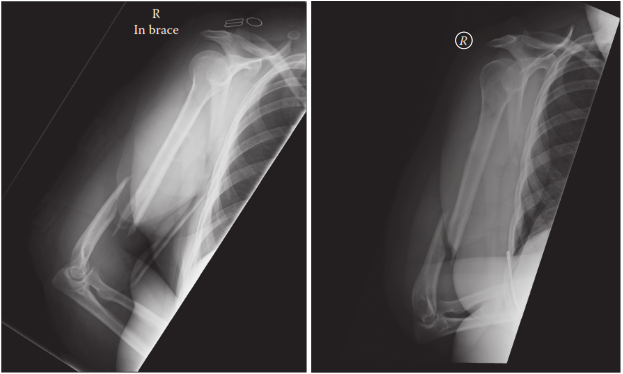

A 32-year-old man is admitted with an injury to his right arm. He has a dense radial nerve palsy. He tells yo…